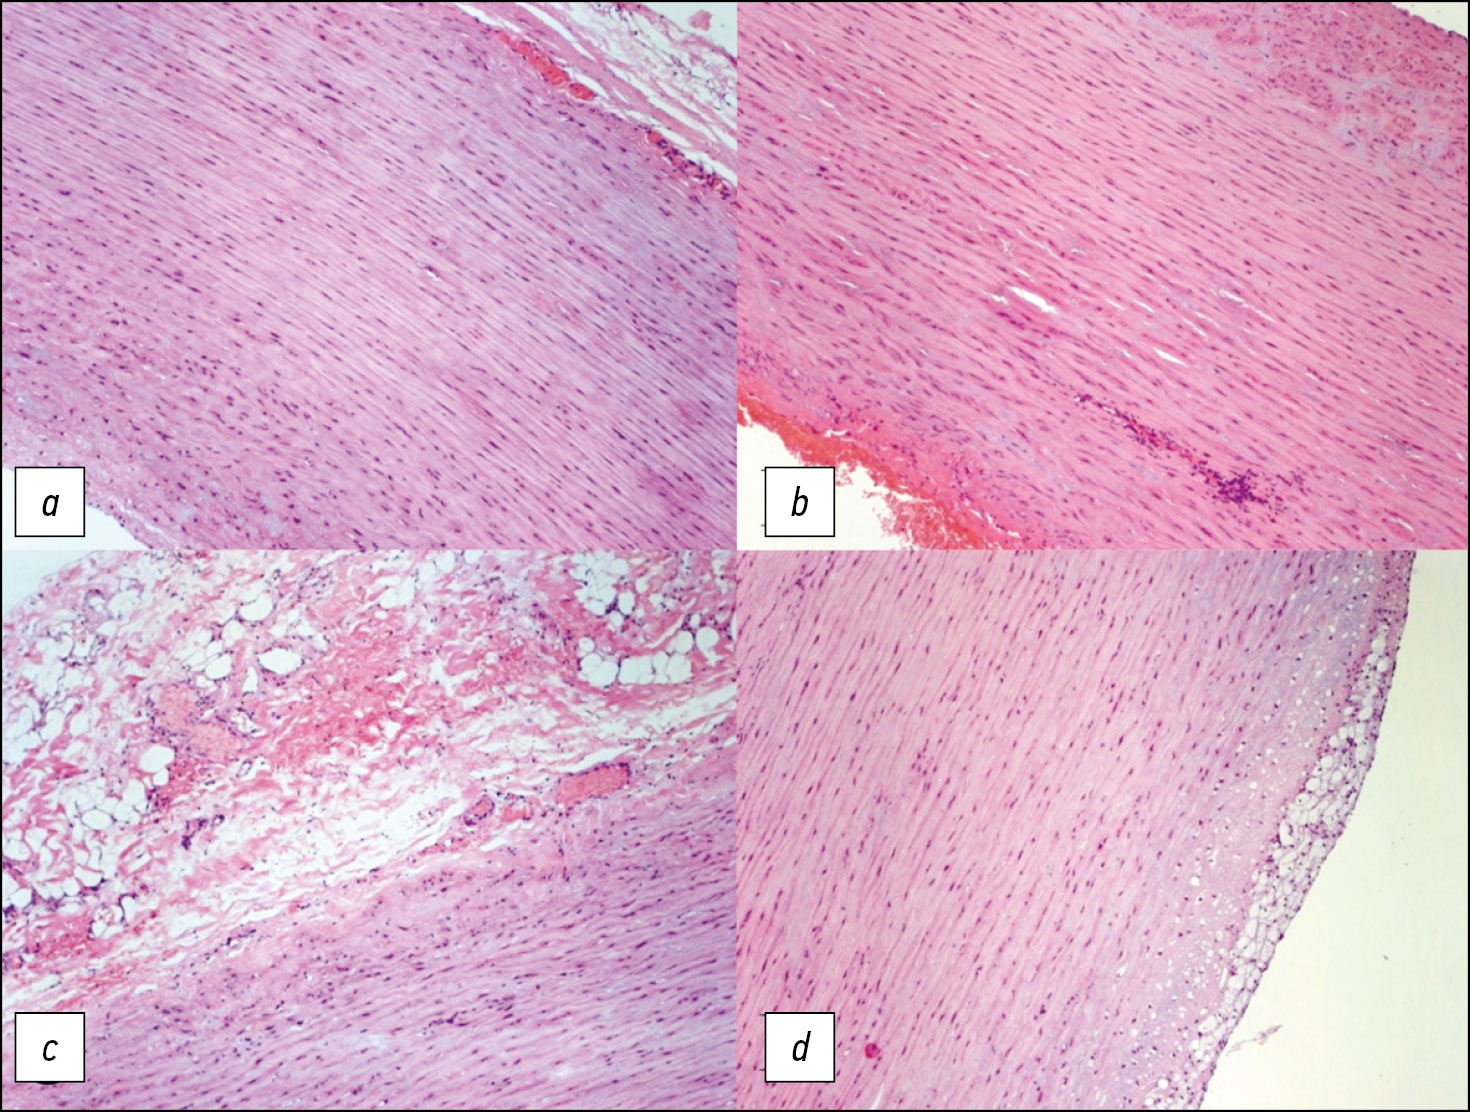

对动脉瘤近端和远端段以及远端切除边缘2 cm的切片进行微观研究,发现中间层广泛破坏,弹性纤维粘液样水肿,弹性膜皱襞平滑。在一些靠近血管外膜的区域,出现中度扩散性血管周围淋巴样浸润的迹象,主动脉壁部分血管的管腔闭塞。在内膜下发现了具有泡沫细胞质的巨噬细胞的局灶性聚集,不突出于表面之上(图3)。

图3。动脉瘤体的近端(a,b)和中间(c)部分。弥漫性血管周围淋巴浸润。切除的主动脉壁的远端部分(d) 。所有图像均显示弹性纤维的破坏,粘液水肿、弹性膜皱襞平滑。

基于组织学检查结果的诊断:非特异性继发性低活动性血管炎,主动脉弹性膜中间层退化。升主动脉瘤。主动脉粥样硬化,脂斑阶段。